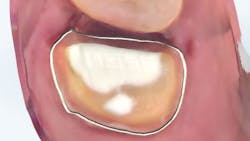

The carious tissue was removed, followed by the endodontic procedure and subsequent placement of the build-up. Despite the deep extent of mesial decay, a clear and accurate scan was achieved (figure 2).

The iTero scanner was able to clearly define the delineation between the soft and hard tissue as can be seen in this image of the digital die trim (figure 3). Radiographs were captured on delivery revealing a clinically acceptable outcome for the patient (figure 4). Direct restorations were completed on teeth Nos. 3 and 4 during this visit.